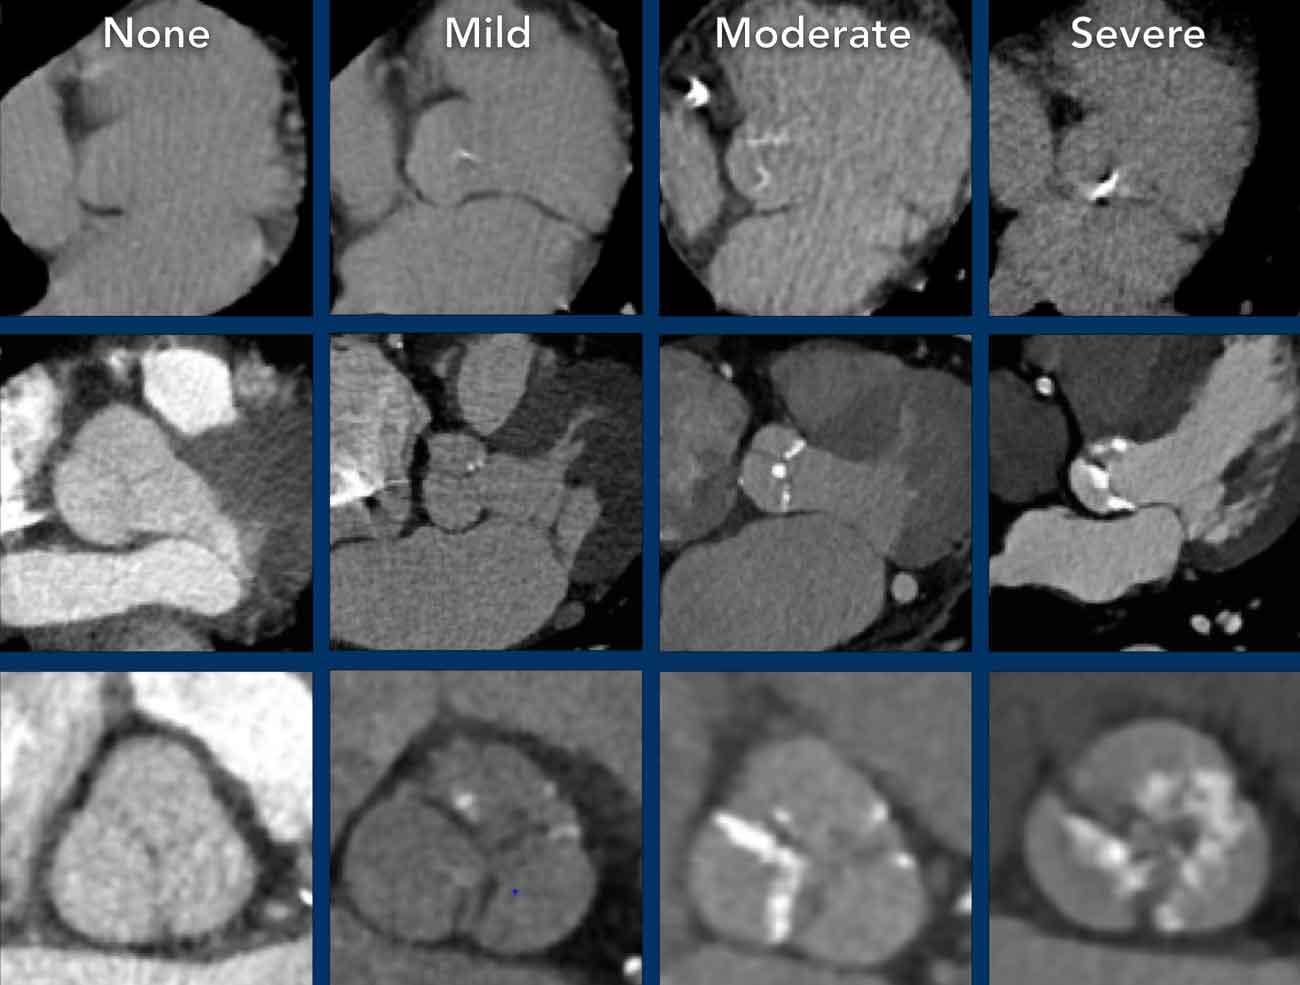

Vôi hóa van động mạch chủ

Vôi hóa van động mạch chủ thường do thoái hóa vôi hóa gây ra và do đó ngày càng được ghi nhận nhiều hơn ở bệnh nhân cao tuổi. Ở bệnh nhân trẻ tuổi, van động mạch chủ hai lá cần được đặt lên hàng đầu trong chẩn đoán phân biệt.

Mức độ vôi hóa van động mạch chủ tương quan với mức độ nặng của hẹp van động mạch chủ.

Khuyến cáo đánh giá định lượng bằng mắt mức độ vôi hóa van động mạch chủ thành nhẹ, trung bình và nặng (hình).

Có thể đưa khuyến nghị vào báo cáo chẩn đoán hình ảnh (xem Hình).

Nếu phát hiện vôi hóa van động mạch chủ, cần khảo sát kích thước gốc động mạch chủ và động mạch chủ đoạn lên.

Vôi hóa cũng có thể xuất hiện ở các vị trí khác trong tim, bao gồm van hai lá hoặc vòng van hai lá, và màng ngoài tim. Tuy nhiên, trong nhiều trường hợp đây là những phát hiện không có ý nghĩa lâm sàng và không cần đưa ra khuyến nghị trong phần kết luận báo cáo.